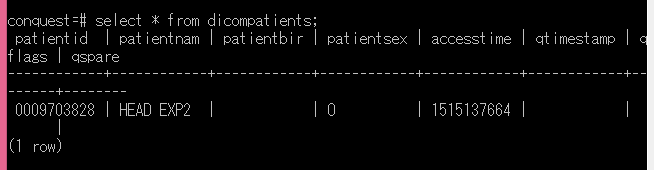

では、中に何が入っているか見てみましょう。

「select * from dicompatients;」と入力してみてください。

Dicompatientsテーブルの中身が表示されました。

PatientNamフィールドに、HEAD EXP2というサンプル名が入っているのが分かります。

これで、問題なくサンプルデータが格納されたことになります。

データベースの設定はこれで終わりです。